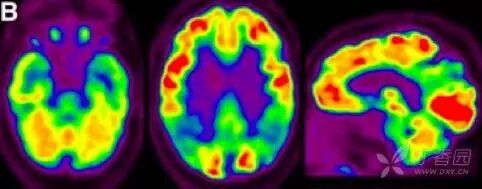

注:正常大脑(左图),轻度阿尔茨海默病(中图),重度阿尔茨海默病(右图)

2.葡萄糖代谢 PET(FDG PET)

FDG PET 用于测量神经元和胶质细胞的葡萄糖摄取情况,被认为是突触功能变化最敏感的指标。AD 患者可出现典型的颞顶区、后扣带回皮质和楔前叶葡萄糖代谢降低,具有 90% 敏感性以识别出 AD 与其他类型痴呆。

也有研究发现,AD 早期颞叶出现高代谢,提示可能为疾病早期代偿表现。携带载脂蛋白 APOEε4 等位基因认知正常受试者也被发现与 AD 相似脑区的代谢异常。因此,作为衡量脑功能改变的指标,FDG PET 对 AD 疾病进展过程中脑功能改变的评估诊断价值更高。

图 3  AD 患者的 18F-FDG PET 成像 7